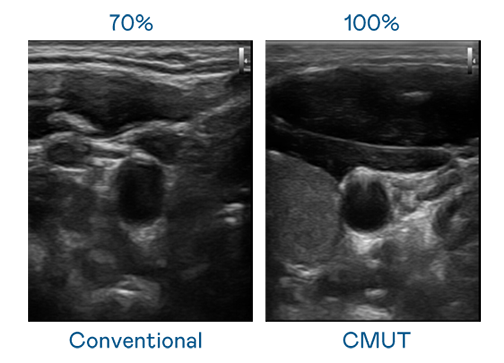

CMUT 技术是一种用电容式微机电元件来产生超音波讯号的技术。与传统 PZT 压电式技术相比,CMUT 频宽增加 30%,更宽频的超音波讯号让影像解析度大幅提升,是实现高影像品质医疗超音波扫描、促进精准医疗发展的关键技术。

超音波影像的解析度高低,首先取决于探头能发出的讯号频宽。7790必发集团 CMUT 可提供高清晰的超音波讯号,提供高频宽、高灵敏度、影像纹理细节更高的超音波影像,协助医护人员缩短影像判读时间及利用精准的医疗影像进行诊断。